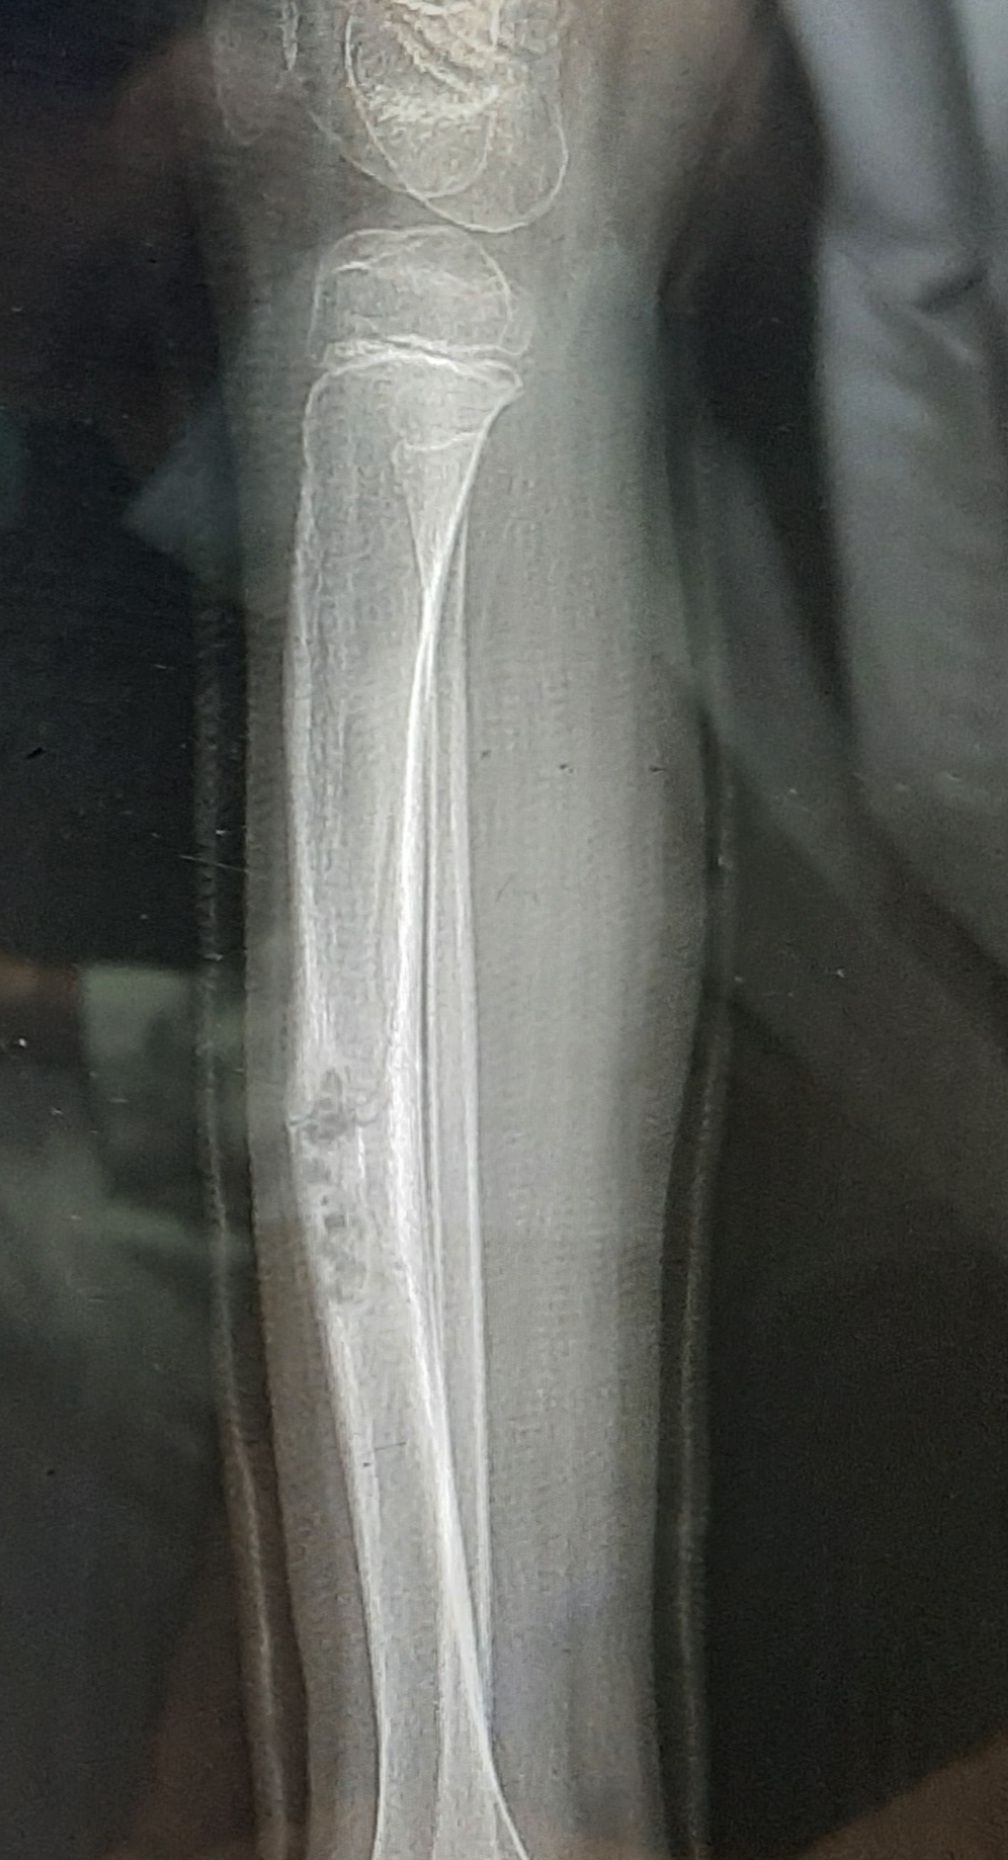

is characterized by: multiple non-ossifying fibromas of the long bones and jawcafé au lait spots intellectual disability kyphoscoliosis hypogonadism or cryptorchidism ocular malformations cardiovascular malformations giant cell granuloma of the jaw axillary and inguinal freckling